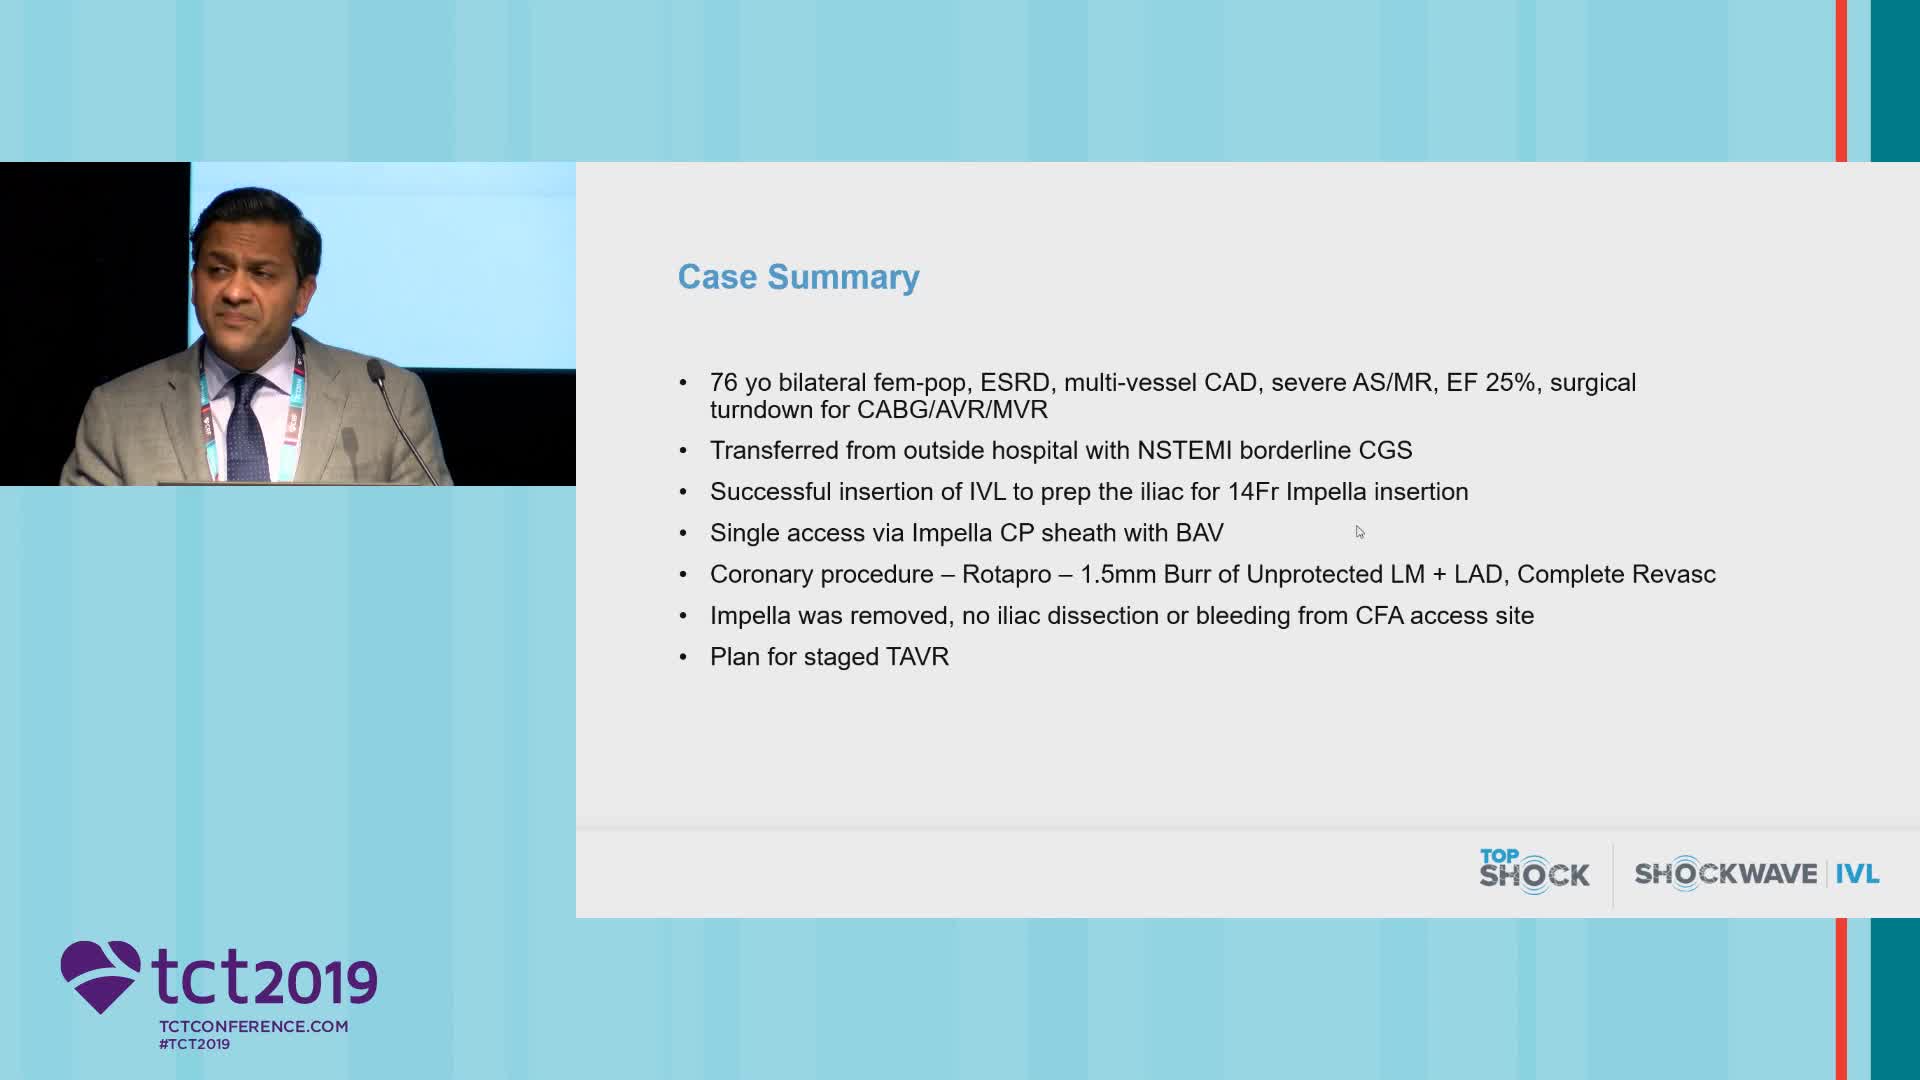

IVL to facilitate Transfemoral TAVI

Simplify your procedures with Intravascular Lithotripsy (IVL) by safely modifying intimal and medial calcium to achieve optimal outcomes while minimising trauma, complications and costs due to its unique MOA.